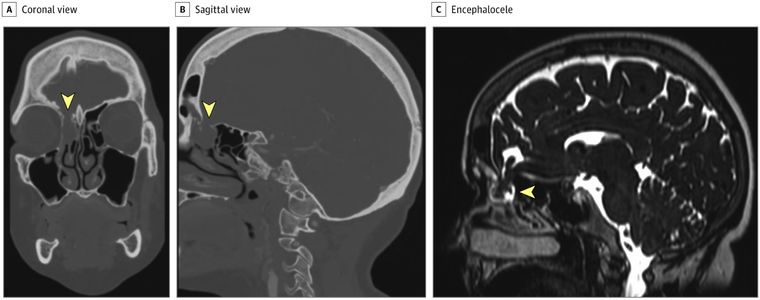

La tomografía computarizada (TC) y la resonancia magnética (RM) identificaron un encefalocele de 1,8 cm que se extendía a través de la fóvea etmoidal derecha hacia el meato medio y un pseudomeningocele del ala esfenoidal derecha.